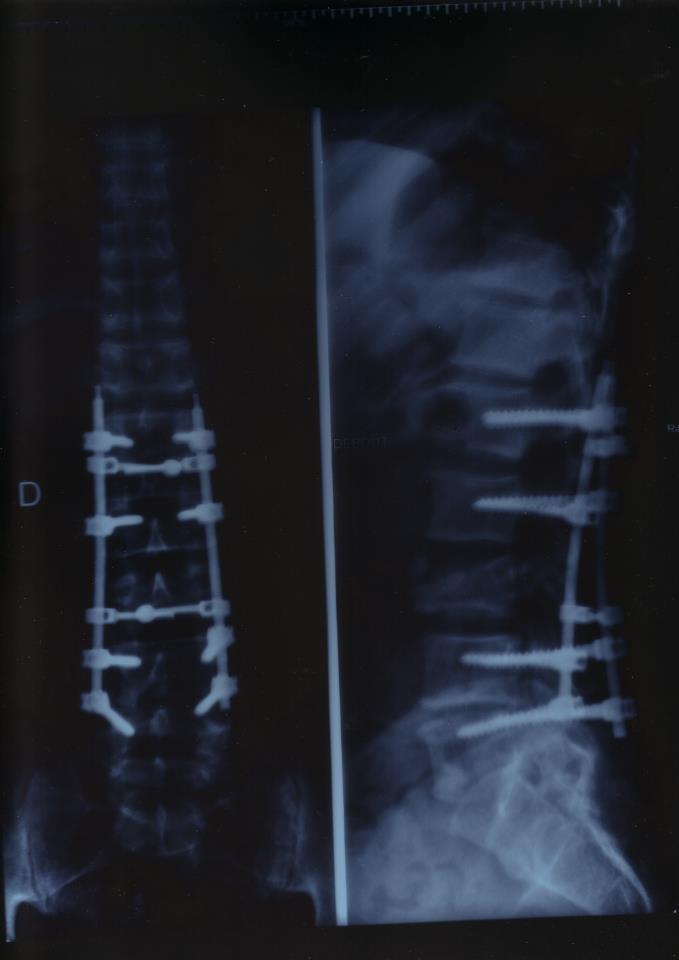

Salut à tous , j'ai 50 ans , je suis un passionné de la marque depuis 1996 . J'ai pratiqué 32 ans de compétitions de Mx et suite à un accident de moto ( à l'entrainement : une chute sur le cul dont la résonance m'a fait une triple fracture de la L3  :cry:  )

J'ai la chance d'avoir toujours l'usage de mes jambes ( lors de la chute elles ne bougeaient plus pendant environ 10 mns. ) et de pouvoir faire de la ballade-enduro avec mes potes !